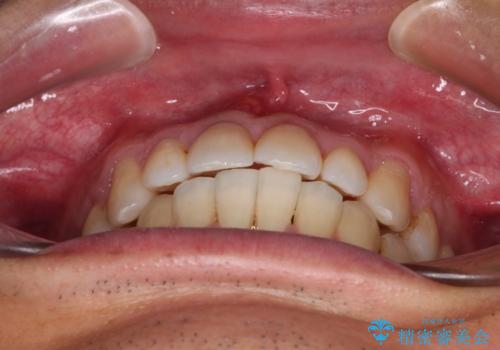

受け口傾向の咬み合わせ 前歯のデコボコをワイヤー矯正で素早く改善

- 前歯の見た目を気にして来院された患者様です。

ワイヤー矯正でもマウスピース矯正でも対応可能とお伝えし、非常に悩まれていましたが、2年後に転勤の可能性が高いとのことで、治療終了までの期間を想定しやすいワイヤー矯正にて治療を行うこととしました。

前歯のクロスバイトは、改善の途中で歯髄壊死を起こすリスクが高くなるため、マウスピース矯正よりもワイヤー矯正をお勧めしております。

この患者様もクロスバイトはあっという間に改善され、1年強で速やかに治療を終えることができました。